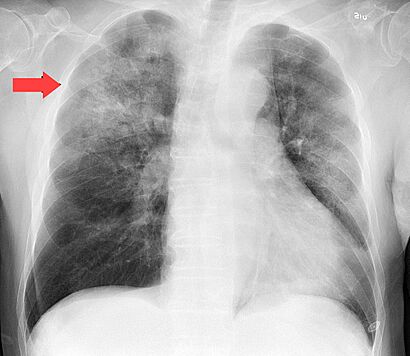

A chest x-ray of a patient with severe viral pneumonia due to SARS